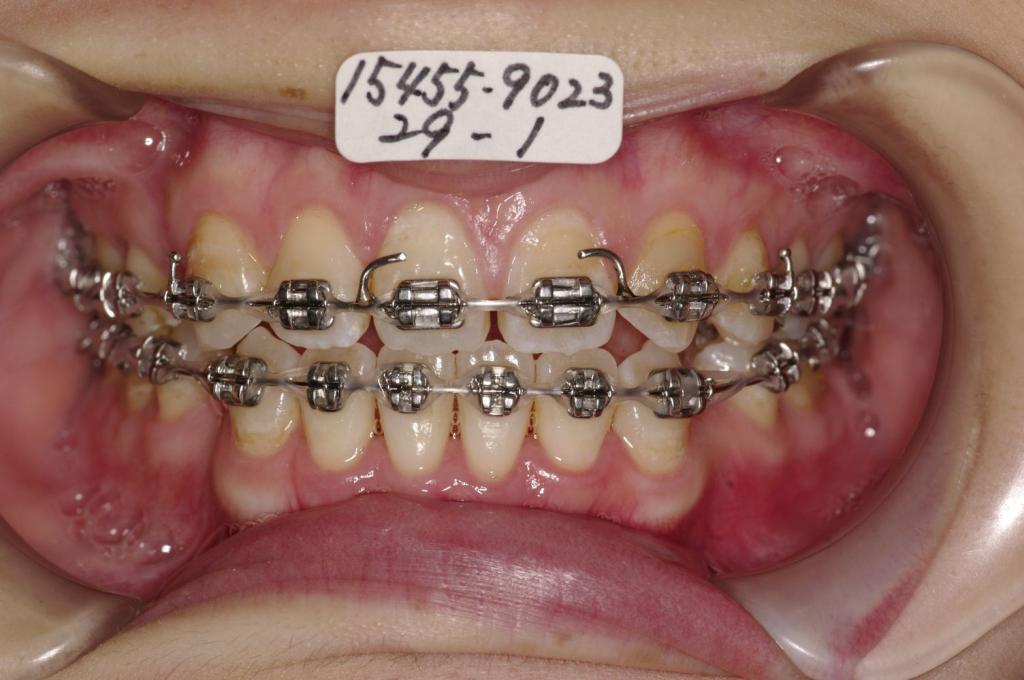

治療前

歯欠損の矯正治療前口内写真NO.141